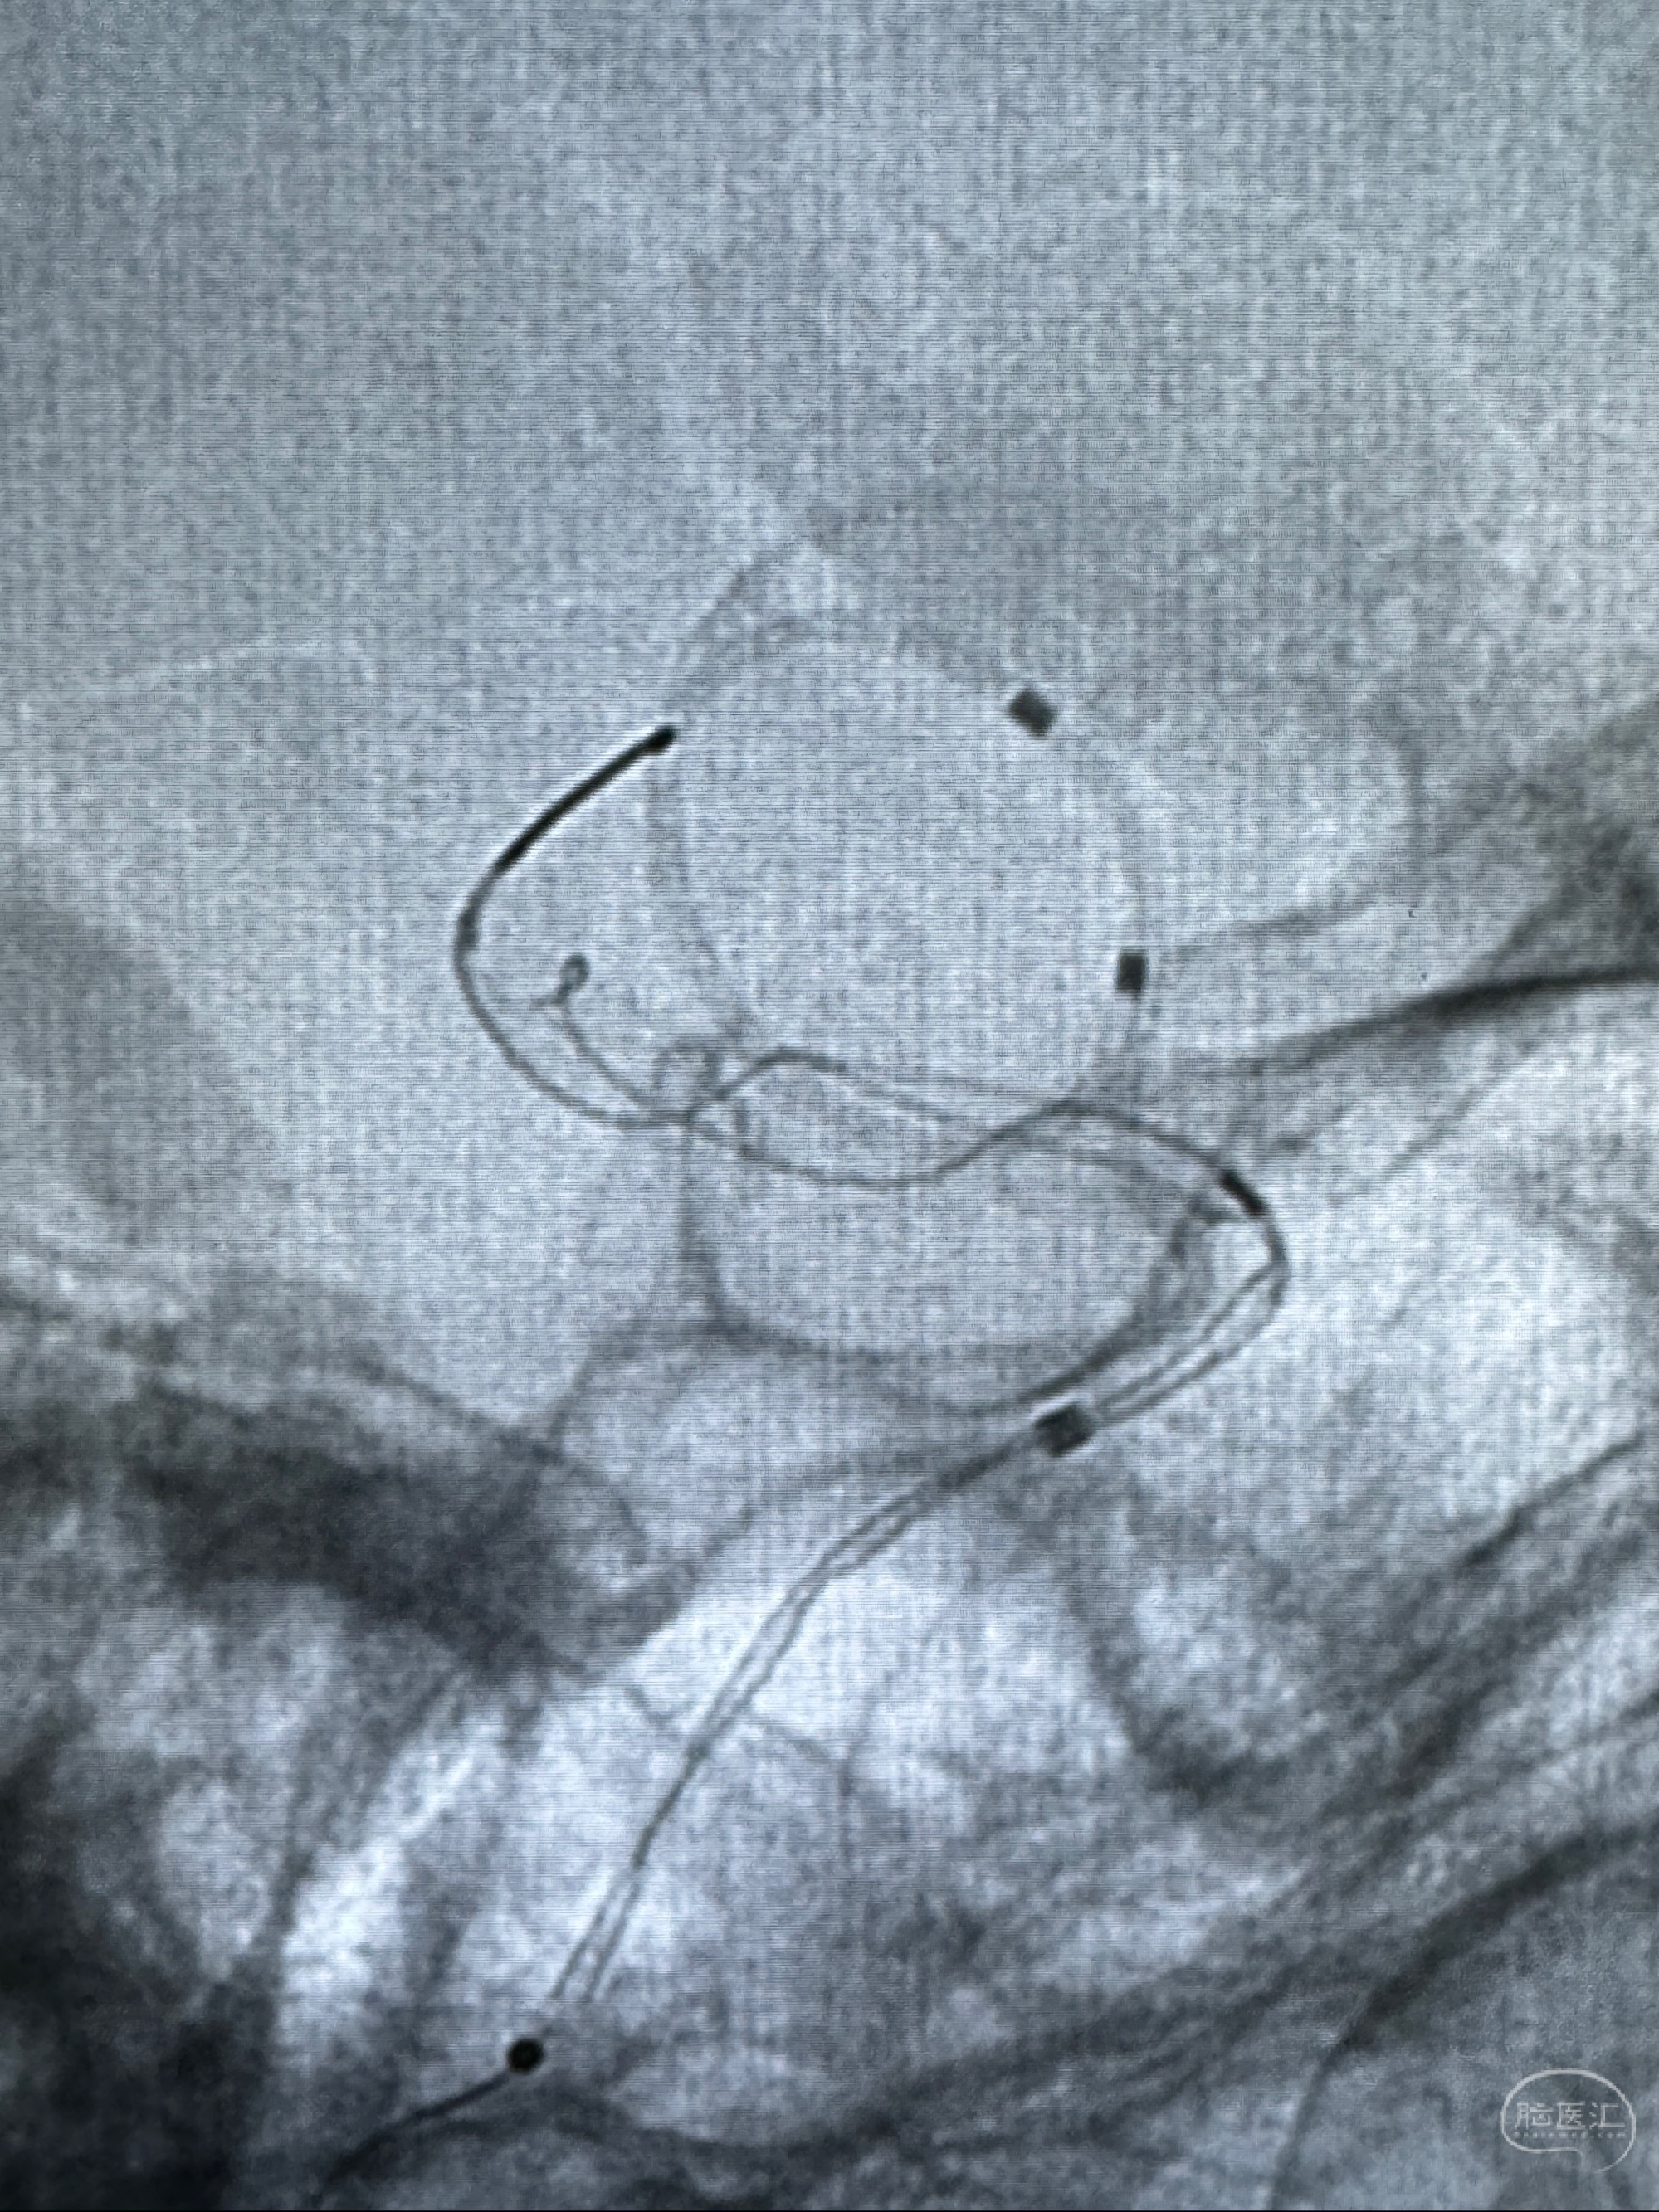

透视可见红圈部分为支架导管的头端

手推冒烟显示支架位置及展开情况,箭头为支架导管的位置

尝试回收支架失败,只能考虑释放支架了

逐帧图像展示歪着脖子释放支架,旁边吩咐助手手机摄影、拍照留像(透视机不能留影像)

接下的视频为释放支架的过程及试图确认支架与血管的关系